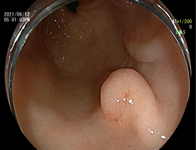

• 小小內(nèi)鏡顯神通  中西結(jié)合瘥頑疾

40歲的廖姐因腹瀉、腹脹3個(gè)月到漳州市中醫(yī)院脾胃病科住院治療。胃腸鏡檢查回報(bào):胃內(nèi)有一黏膜下腫物。腹部CT平掃+增強(qiáng)提示:胃竇體交界處局部向腔內(nèi)膨隆突起,未向腔外生長,與胃竇同步強(qiáng)化。檢查結(jié)果令廖姐寢食難安。    林震群主任考慮該腫物為黏膜下10x10mm半球形腫物,表明光滑,觸之活動(dòng)度尚可,經(jīng)科室治療小組討論后決定對廖姐實(shí)施內(nèi)鏡下黏膜下腫物剝離術(shù)(ESE),手術(shù)過程十分順利,術(shù)后病理提示良性病變。廖姐懸著的心終于可以放下了。          ...